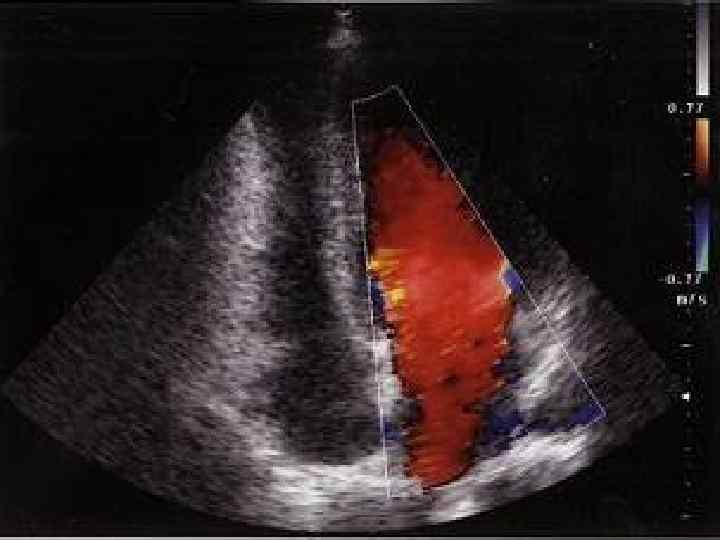

Диастолическая функция ЛЖ Диастолическую функцию ЛЖ оценивают по результатам исследования трансмитраль ногодиастолического кровотока в импульсном допплеровском режиме. Определяют: 1) максимальную скорость раннего пика диастолического наполнения (Vmax Peak E); 2) максимальную скорость трансмитрального кровотока во время систолы левого предсердия 1 (Vmax Peak A); 3) площадь под кривой (интеграл скорости) раннего диастолического наполне ния (MVVTI Peak E) 4) предсердной систолы (MV VTI Peak A); 5) отношение максимальных скоростей (или интегралов скорости) раннего и позднего наполнения (Е/А); 6) время изоволюмического расслабления ЛЖ — IVRT (измеряется при одновременной регистрации аортального и трансмитрального кровотока в постоянно волновом режиме из апикального доступа); 7) время замедления раннего диастолического наполнения (DT).

Vmax Peak E Vmax Peak A Е/А IVRT DT 0, 62 м/с 0, 35 м/с 1, 5 -1, 6 70 -75 м/с 200 мс